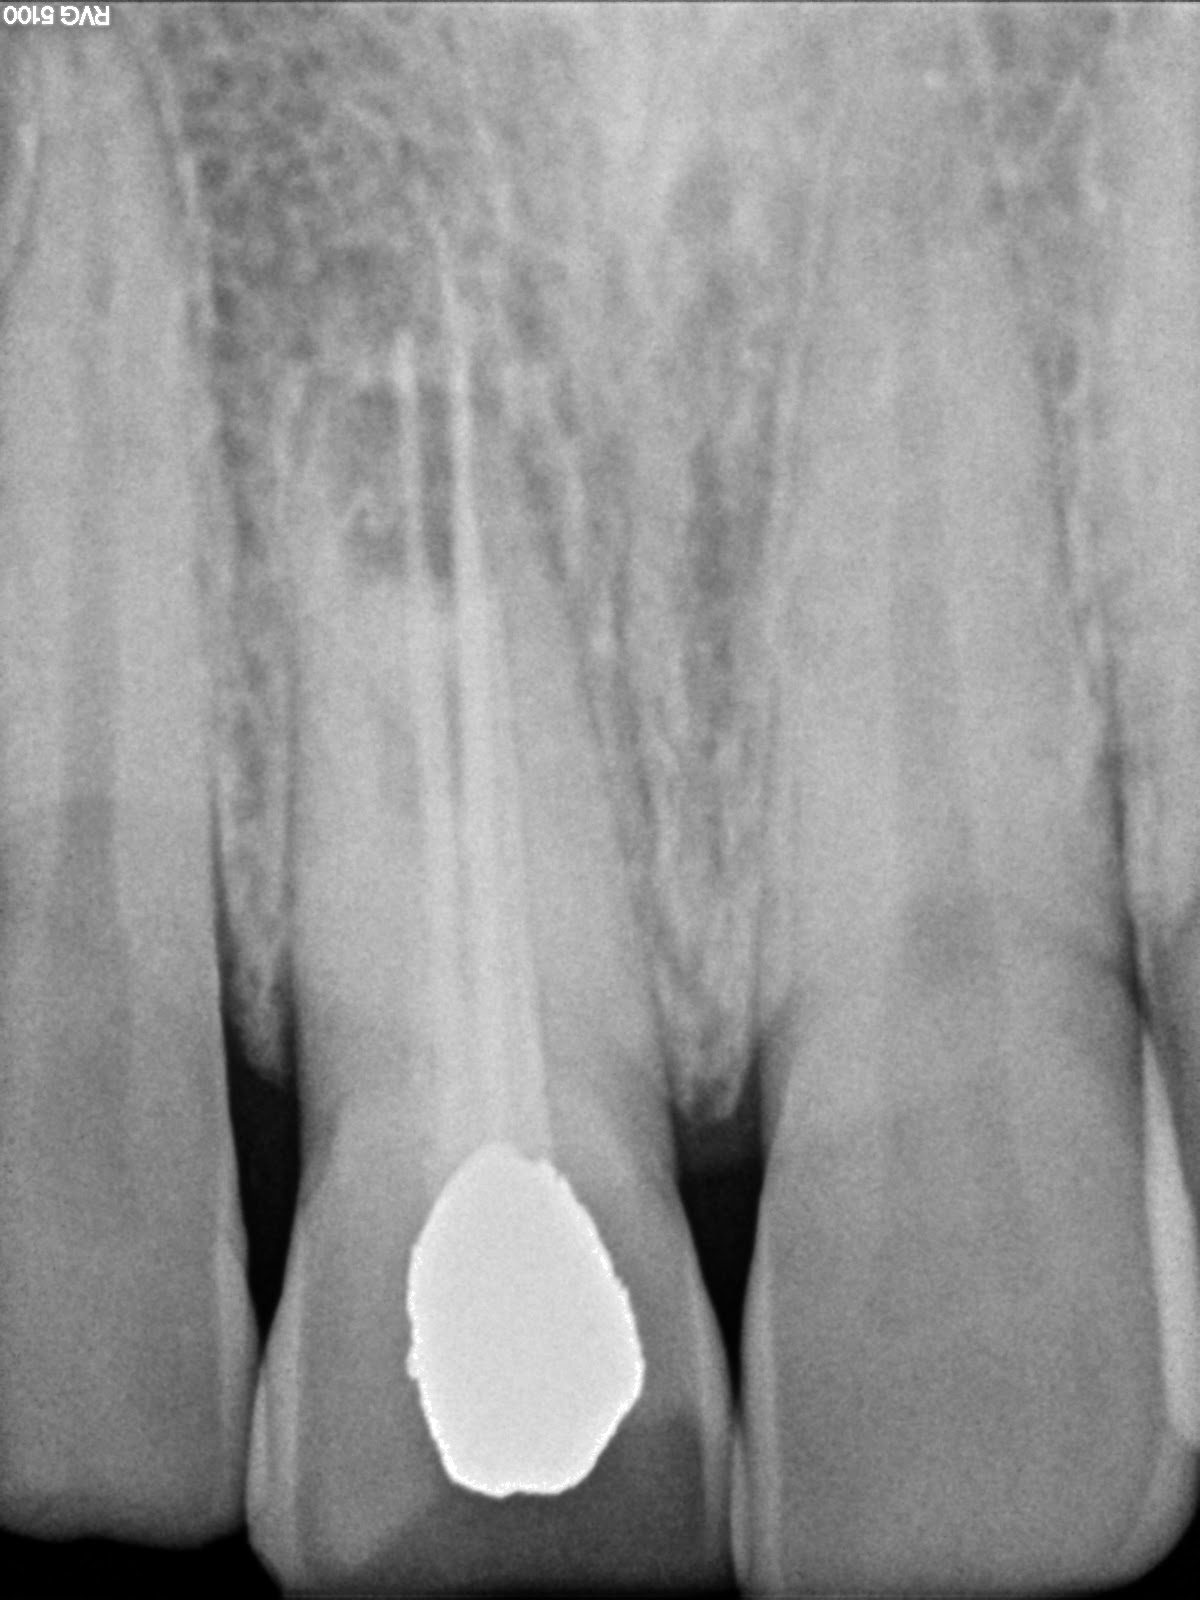

Endodontics Re rootcanal treatment with open apex central incisor Endodontic Treatment Open Apex the open apex can be defined as an unusually wide apical foramen of a root, making it challenging to prepare an. this study reports two clinical cases of apical plug placement in teeth with pulp. the main purpose of endodontic treatment is to accomplish obturation of the root canal space completely and prevention of re. the. Endodontic Treatment Open Apex.

Endodontics Re rootcanal treatment with open apex central incisor Endodontic Treatment Open Apex the main purpose of endodontic treatment is to accomplish obturation of the root canal space completely and prevention of re. the treatment of an immature permanent tooth with a blunderbuss canal, one of the two types of open apex, can be. the golden rule of endodontic treatment is to remove all the debris, shape the root canal. Endodontic Treatment Open Apex.